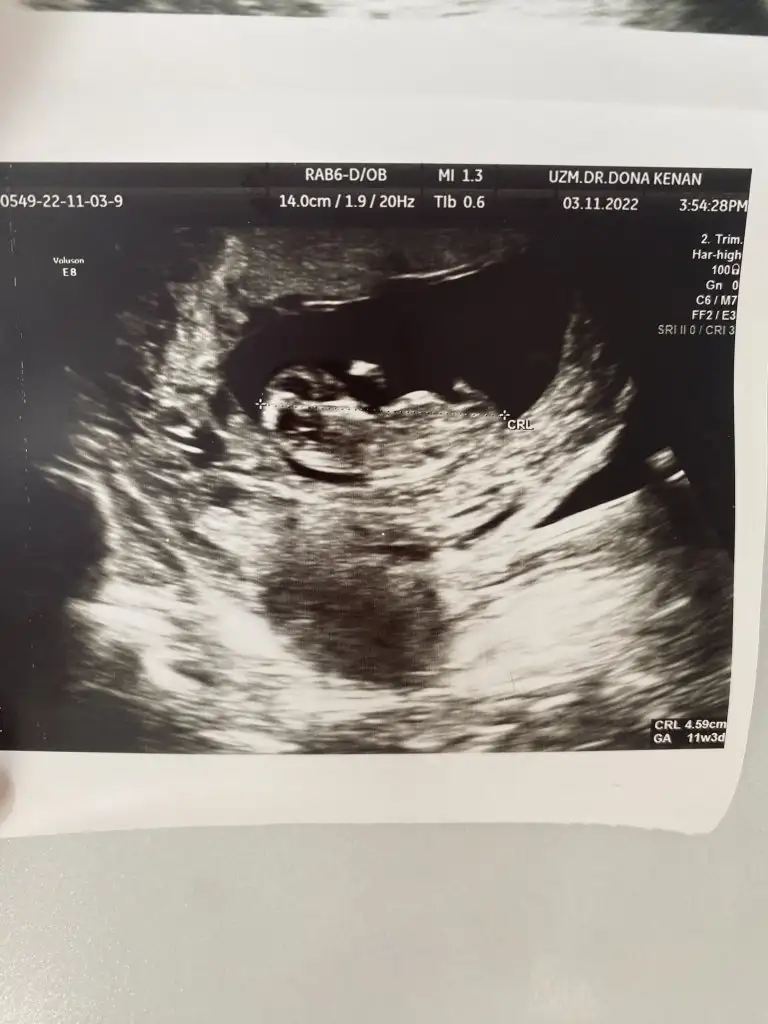

Merhaba ben bugün itibariyle 14 haftalık gebeyim. 11. Haftada perinatolog erken ama bebeğin erkeğe benziyor dedi. 12 de doktorum da aynı şeyi söyledi. Ama 12+4 de gittiğim ayrıntılı ultrasonda nub teorisine göre yüzde 70 kız dedi. Hatta biz erkeğe benzettiler deyince yok yok kız çoğunlukla da bu teori doğru çıkıyor dedi. Biz de kız dedik herkese. Bugün 14 hafta oldum kontrolümde kendi doğum uzmanım sırtı dönük ama bşr çıkıntı var kordon da olabilir erken ama ben erkek tahmin ediyorum dedi. Yine de kordonla karışabilir dedi. Artık iyice kafam karıştı. Sizin fikriniz ne? Benzer birşey yaşayan varsa paylaşır mısınız? Ultrason fotoğrafı bırakıyorum anlayan baksın lütfen.